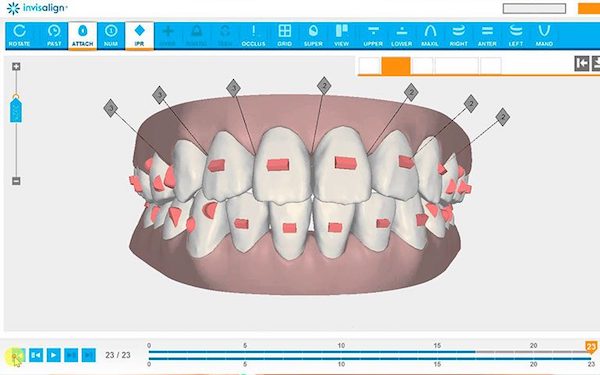

2. Impresiones y ClinCheck

Las férulas de Invisalign se confeccionan a medida de la boca de cada paciente. Para ello, tomamos impresiones con el escáner intraoral iTero. Con estos registros, y gracias al software ClinCheck, podemos crear un plan de tratamiento virtual en 3D que nos permitirá planificar los micromovimientos a los que van a ser sometidos tus dientes, así como mostrarte el aspecto que tendrán tras finalizar el tratamiento.

¿Qué son los ataches y para qué sirven?

Los ataches son unos relieves de composite que se adhieren a los dientes y que hacen que el sistema de Invisalign sea mucho más efectivo, ya que los alineadores por sí solos no pueden hacer los movimientos y necesitan estos relieves para poder hacer más fuerza y que los dientes giren hacia la posición que deseamos.

Existen distintos tipos de ataches que varían en el tamaño y en la forma así como también va a variar su uso según la finalidad que se tenga para los mismos. Por eso, al igual que las férulas, son un sistema personalizado. Es muy común que una persona no lleve los mismos ataches durante todo el tratamiento, ya que estos se irán cambiando en función de las necesidades de cada etapa.

Una vez finalizado el tratamiento, quitaremos todos los ataches de los dientes.

¿Cómo funciona el ClinCheck?

Se trata de un software que va a predecir cómo será todo el tratamiento. En él se podrán ver todos los movimientos que van a hacer los dientes a lo largo del tiempo, lo que te permitirá ver el resultado final y la sonrisa que tendrás una vez termines el tratamiento.